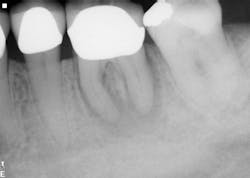

The six-month recall showed nearly complete bone and furcation healing (figure 2). There is still some attachment loss on the straight buccal, but no. 31 remains asymptomatic and in good service.